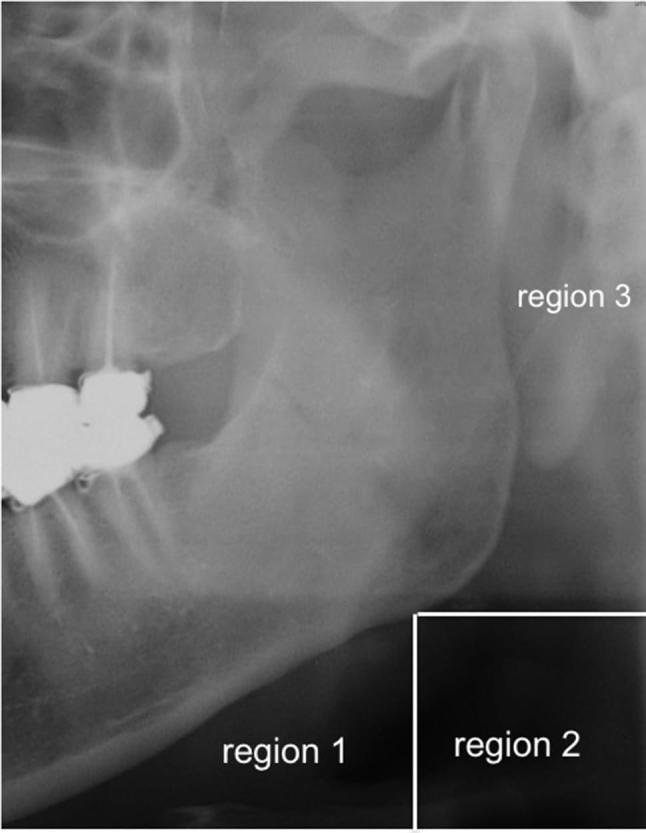

Prior to the cumulative study, interobserver agreement was calculated by κ statistics. We randomly selected 200 panoramic radiographs and CT images of 200 patients. Two radiologists (AT and CS) independently evaluated the presence of lingual tonsilloliths on those images. The interobserver κ was 0.86 (almost perfect) for panoramic radiographs and 1.00 (perfect) for CT images, respectively. This result tells that the interobserver difference might be negligible in detecting lingual tonsilloliths. Therefore, the complete evaluation for 2244 patients was performed by a single radiologist (AT). The presence of lingual tonsilloliths on panoramic radiographs was evaluated as follows. The locations of tonsilloliths were classified into two categories and three regions (Figure 1). Category 1 was defined as calcifications that were superimposed over the mandible. Category 2 was defined as calcifications that were superimposed over the soft tissue surrounding the mandible. Category 2 was divided into three regions as follows: inferior to the body of the mandible (region 1), posteroinferior to the angle of the mandible (region 2) and posterior to the ramus of the mandible (region 3). Then, the size of lingual tonsilloliths on panoramic radiographs were evaluated. To evaluate the location of lingual tonsilloliths relative to the tongue, the soft tissue shadow that coincides with the anterior border of the oropharyngeal airway on panoramic radiograph was defined as the posterior edge of the base of tongue. The distance between the center of lingual tonsilloliths and the posterior edge of the base of tongue was measured (Figure 2). We selected the largest tonsil as the representative one in patients with multiple tonsilloliths. In the measurement on panoramic radiographs, we calculated based on the pixel size, which was 96 × 96 µm on DICOM format. As the lingual tonsilloliths were located apart from the focal trough, we could not apply the magnification factor of this apparatus, which was 1.3 on the focal trough. Therefore, we did not correct the dimensions on panoramic radiographs.

Figure 1.

Locations of lingual tonsilloliths that were superimposed over the soft tissue surrounding the mandible on panoramic radiographs. Region 1: inferior to the body of the mandible; Region 2: posteroinferior to the angle of the mandible; Region 3: posterior to the ramus of the mandible.

On panoramic radiographs, lingual tonsilloliths were predominantly superimposed over the soft tissue surrounding the mandible (category 2) (Table 3). They were located in region 1 (inferior to the body of the mandible) in 16 individuals (48.5%) (representative images, Figure 3a–c), region 2 (posteroinferior to the angle of the mandible) in 15 individuals (45.5%) (representative images, Figure 3d–f) and region 3 (posterior to the ramus of the mandible) in 1 individual (3.0%) (representative images, Figure 3g–i). Lingual tonsilloliths were also superimposed over the mandible (category 1) in one individual (3.0%) (representative images, Figure 3j–l).